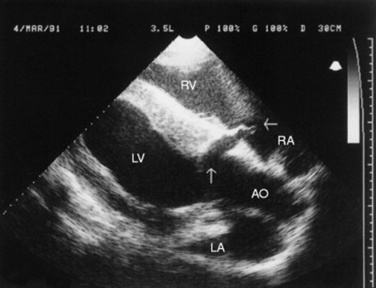

Aneurysms or pseudoaneurysms may be visualized radiographically as soft-tissue density masses continuous with a vessel wall (true aneurysm) or extending outward from a vessel wall (false aneurysm).203,204 However, the majority of the aneurysms involving the aorta and aortic root are not visible radiographically. Echocardiography is useful in the diagnosis of aneurysms involving the aortic root (Fig. 30-26).206-209 Angiography can be used in the diagnosis of peripheral vessel swelling or suspected thrombosis but is of little use in diagnosis of aneurysms of major vessels in adult animals. Ultrasonography may be used for the diagnosis of aneurysms or thrombosis of major arteries and peripheral vessels. In aortoiliac thrombosis of horses, ultrasound has been used to determine the origin of the thrombus and the extent of occlusion of the involved arteries (Fig. 30-27).218 Abdominal ultrasonography of the upper left flank dorsal to the left kidney has been used to diagnose aortoiliac thrombosis in calves.215 Diagnostic ultrasound has been used to detect thrombi in the caudal vena cava in cattle.219,220 Although the occluding thrombus is not imaged, the detection of a distended oval or round caudal vena cava, rather than the normal triangular vessel, in the eleventh and twelfth intercostal spaces is consistent with this diagnosis in cattle. Thrombi have been detected ultrasonographically in the hindlimb in both horses and cattle.221-224 Jugular vein thrombophlebitis has also been diagnosed ultrasonographically in both horses and cattle (Fig. 30-28).225,226 Similarly, diagnostic ultrasound has been used to image the cranial mesenteric artery, its branches, and the aorta in horses with verminous arteritis.227 Aneurysms appear as dilated vascular structures or vascular outpouchings continuous with the vessel wall,205 whereas a thrombus is apparent as a hypoechoic to echogenic mass within a blood vessel.226 Cavitation of an occlusive thrombus is suggestive of septic thrombophlebitis (see Fig. 30-28), whereas a nonseptic thrombus usually has a homogeneously hypoechoic to echoic appearance.226 Complete occlusion of the vessel can be determined ultrasonographically, or flow within an aneurysm or alongside a thrombus determined. Doppler ultrasound provides a more sophisticated method for determining blood flow and vessel patency. Computer-assisted radiographic techniques such as computed tomography and digital subtraction angiography may also be useful but have not yet been widely used in large animals. The latter methods may be limited in usefulness by the size of large animals and the cost of the equipment and procedures.

image

Fig. 30-26 Two-dimensional echocardiogram of a horse with a ruptured sinus of Valsalva aneurysm. Not the defect in the right side of the aorta at the sinus of Valsalva (vertical arrow) extending into the right atrium (horizontal arrow). The right atrium (RA), right ventricle (RV), left ventricle (LV), left atrium (LA), and aorta (AO) can be seen in this left ventricular outflow tract view.

The most common outcome of aneurysm of a major vessel is thought to be rupture. Rupture of sinus of Valsalva aneurysms into the right atrium, right ventricle, and interventricular septum has been reported in the horse.206-208 Ventricular tachycardia often occurs with rupture of an aortic sinus of Valsalva aneurysm and dissection into the interventricular septum.207,208 Unruptured aneurysms may have other complications such as thrombosis or embolization of the thrombus. The frequency of rupture or embolic showering from thrombosis is unknown in animals.

Aneurysms of major vessels carry a guarded to grave prognosis because surgical correction is rarely attempted and spontaneous rupture is thought to be relatively common. Intact aneurysms of the sinus of Valsalva can be detected echocardiographically, and once an aneurysm has been detected, the horse should be removed from all athletic competition because of the risk of rupture.205